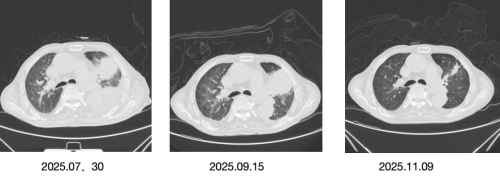

一个半月后复查,CT片子上的变化让所有人欣慰:肺部的阴影明显缩小了。肿瘤标志物的指标也一路下降。靶向药,像一枚精准的导弹,在他体内起到了关键作用。